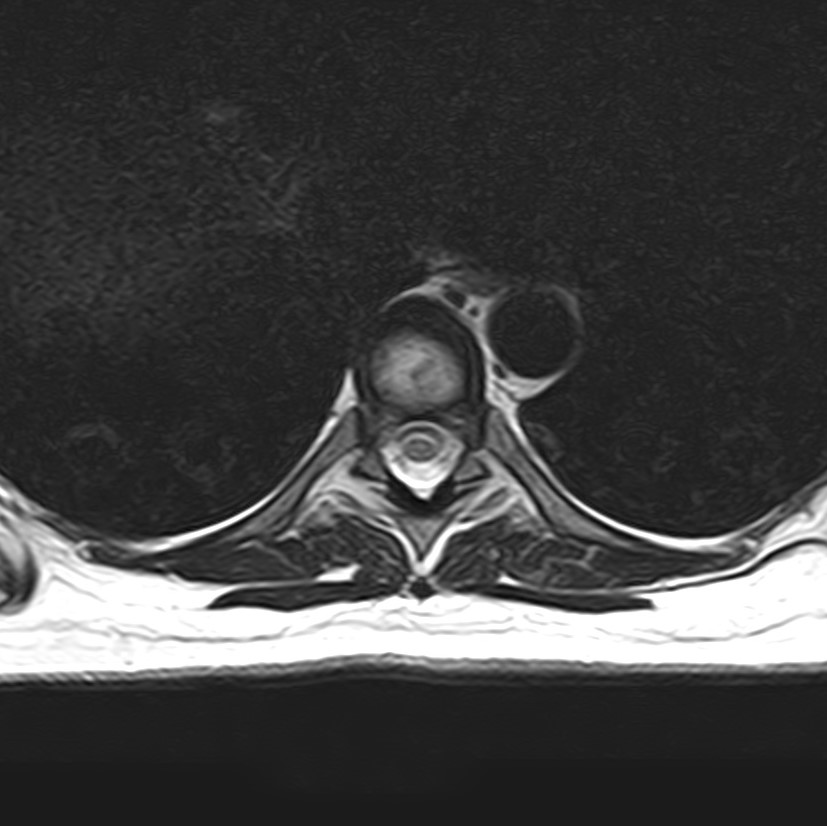

МРТ является современным высокоточным исследованием грудного отдела позвоночника, с помощью которого можно диагностировать различные заболевания, в том числе воспалительные, дегенеративные и опухолевые процессы. Преимуществом данного метода является его безопасность (отсутствие рентгеновского излучения), безболезненность, неинвазивность, при этом высокая информативность.

Клиника «Доступная медицина» оснащена новейшим томографом экспертного класса TOSHIBA VANTAGE TITAN 1,5 Тесла, который позволяет получать превосходные изображения с мельчайшей детализацией всех структур исследуемой области. Это позволяет ставить точный диагноз и выявлять различные заболевания позвоночника на самой ранней стадии.

С помощью МРТ грудного отдела выявляют следующие заболевания позвоночника:

• новообразования;

• степень повреждения спинного мозга в случае переломов тел позвонков;

• грыжи Шморля;

• травматические повреждения тел позвонков и остистых отростков (трещины, переломы, смещения и пр.) — при недоступности КТ;

• разрывы, растяжения связок;

• травмы спинного мозга, нервных корешков;

• протрузии;

• грыжи межпозвонковых дисков;

• остеохондроз позвоночника;

• стеноз спинномозгового канала;

• сосудистые патологии;

• остеомиелит, спондилодисцит;

• рассеянный склероз;

• спондилоартроз;

• спондилез.